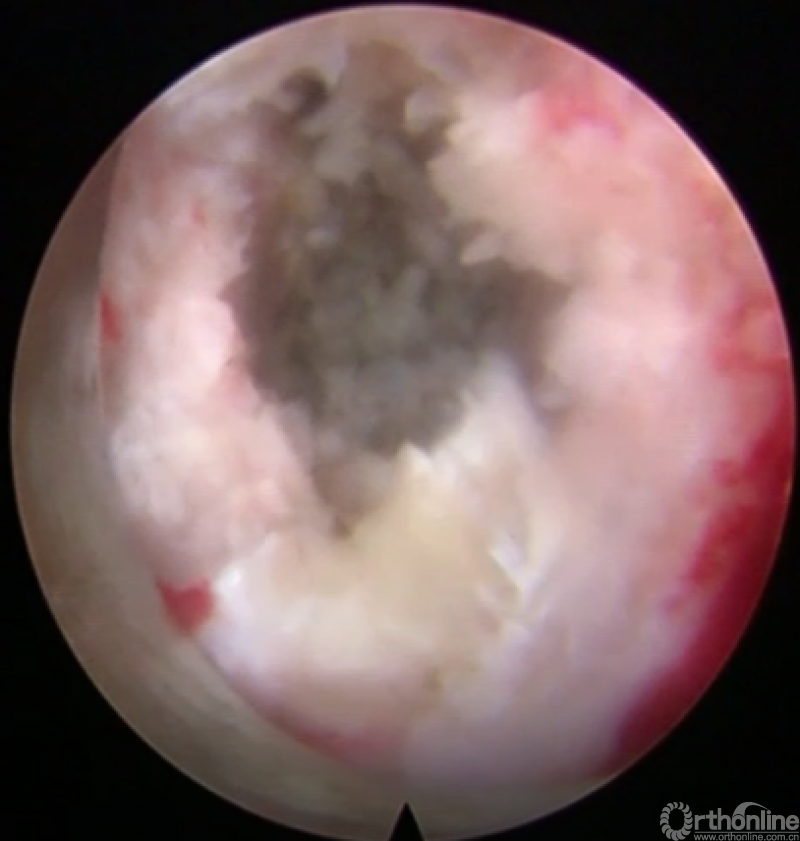

第六步“切”:切除椎间盘;

第七步“牵”:神经拉钩牵拉保护神经根;

第八步“铰”:铰刀置入处理上下终板(刮勺置入处理终板);

第九步“填”:椎间隙填塞植骨;